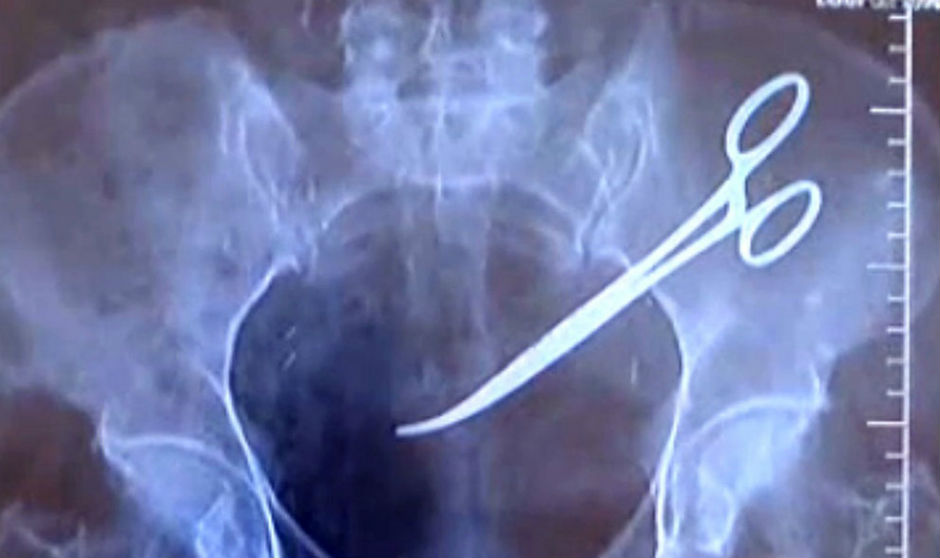

Por otro lado, aunque menos comunes, también están los olvidos de instrumental quirúrgico (sobre todo vendas o algodones, pero también agujas, pinzas e incluso tijeras) dentro del cuerpo del paciente tras una operación. Esto es precisamente lo que le pasó en 2011 a un vecino de Gran Canaria que, aquejado de un fuerte dolor abdominal, descubrió que el cirujano que le había intervenido dejó en su interior dos pinzas quirúrgicas. Este error médico provocó al paciente una perforación con desgarro en el bazo y una pérdida masiva de sangre.